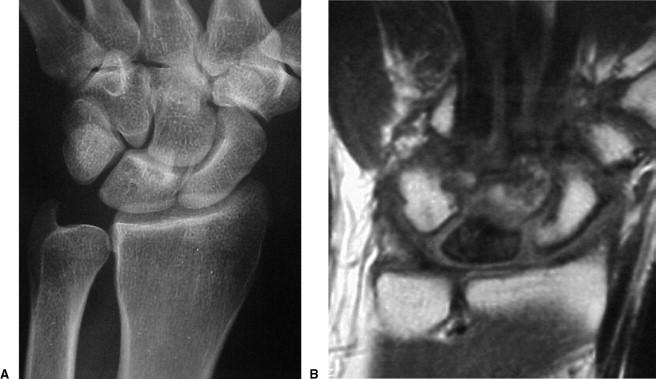

Stage III 부터는 주상골도 영향을 받기 시작하며 회전을 하거나(IIIA, cortical ring 관찰가능), carpal height 가 줄어드는 것을 확인할 수 있습니다. (IIIB), IIIA 까지는 II와 치료를 거의 동일하게 하지만, IIIB 부터는 Proximal row carpectomy 나 STT, SC fusion 등을 시행해 볼 수 있습니다.

치료 중에 IIIB 부터 시행하는 치료는 아래와 같습니다.